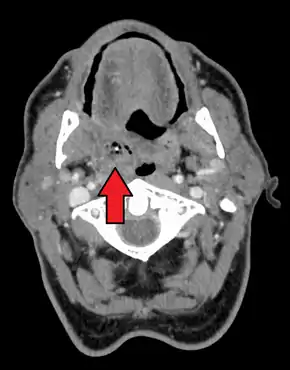

Diagnosis is usually based on the symptoms.[1] Medical imaging may be done to rule out complications.[1] Medical imaging may include CT scan, MRI, or ultrasound is also useful in diagnosis.[1]